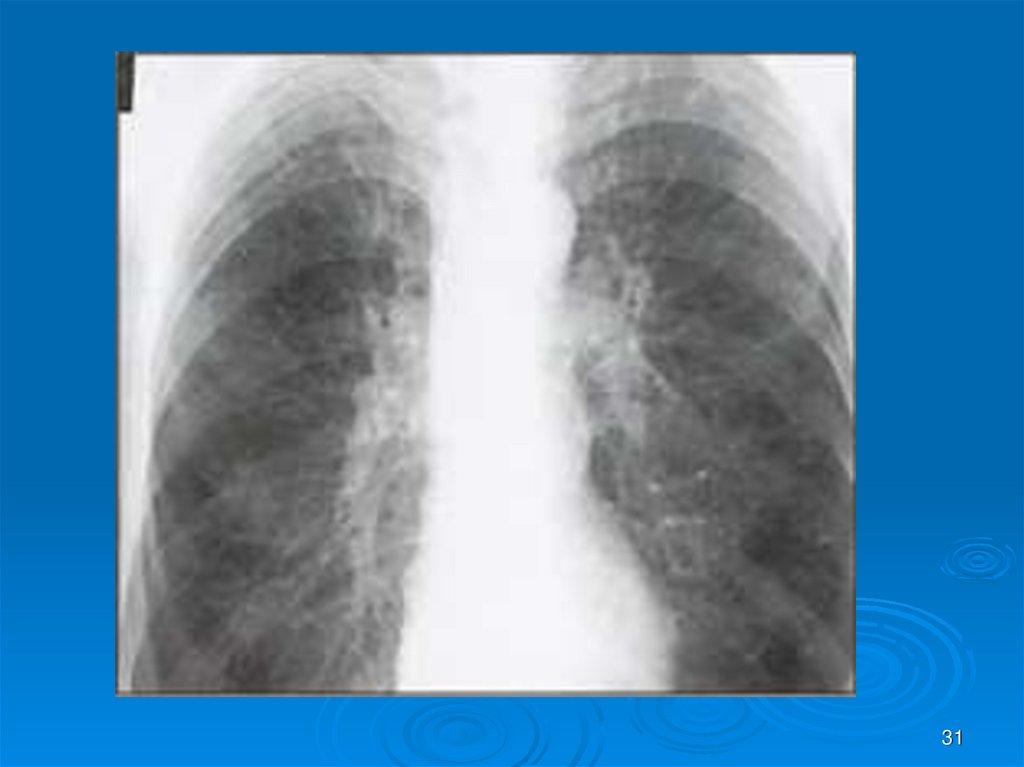

31.

31